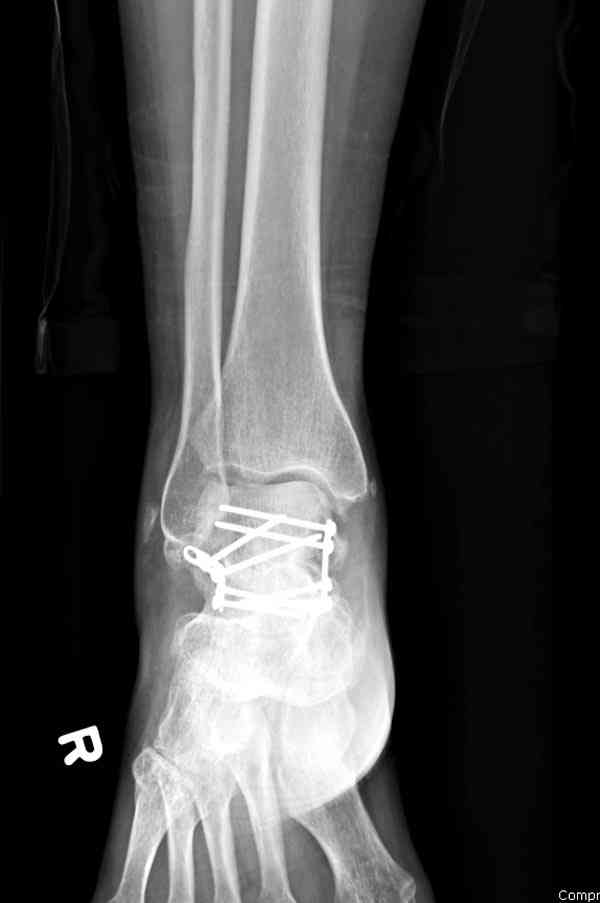

Случай с множественным оскольчатым переломом тарана оперированный из двойного доступа.

Через 14 мес.:

В вашем случае доступ через перелом медиальной лодыжки, обычный доступ через остеотомии лодыжки, где имеется возможность прямой репозиции тарана, после фиксации шурупами, лодыжки фиксируются обычным 2х лодыжечным методом.

При в первом типе придерживаемся закрытой репозиции, а у всех остальных в зависимости от смещения предпочитаем открытую репозицию, фиксация шурупами или пластиной. Пластина 2.4 мм более предпочтительна для удержания мелких костных осколков.